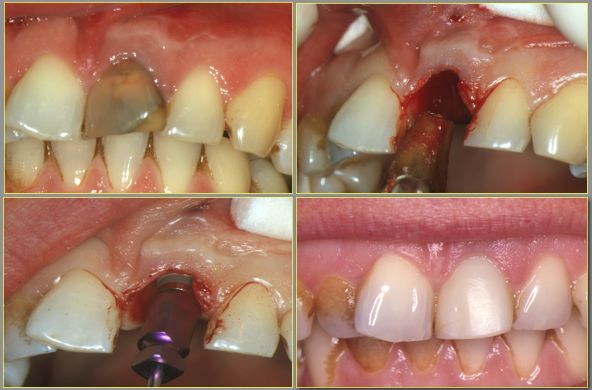

– Nouvelle technique : implantation immédiate

Une nouvelle option consiste à mettre en place immédiatement après la pose de l’implant une couronne provisoire pour éviter le port d’une prothèse amovible inconfortable et permettre par ailleurs de conserver le volume initial des tissus (os et gencive). Les conditions anatomiques doivent être idéales avec en particulier un ancrage osseux solide de l’implant. La technique peut même être poussée jusqu’à pratiquer dans le même temps opératoire l’extraction de la dent, la mise en place de l’implant et de la couronne provisoire :

Les avantages de ce protocole sont nombreux, avec en particulier la suppression d’une prothèse provisoire mobile, la diminution du nombre de chirurgie (plus qu’une seule séance) et un rendu esthétique optimisé du fait de la conservation instantanée des structures osseuses et gingivales